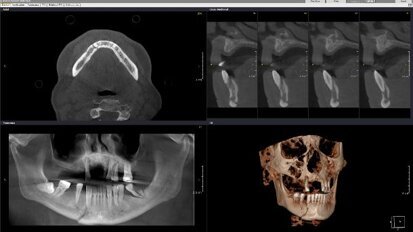

Webinar: Expert gives insights into CBCT-based diagnosis of trauma cases

LEIPZIG, Germany: Cone-beam computed tomography (CBCT) has taken on greater significance over the past few years and has improved the standard of dental ...